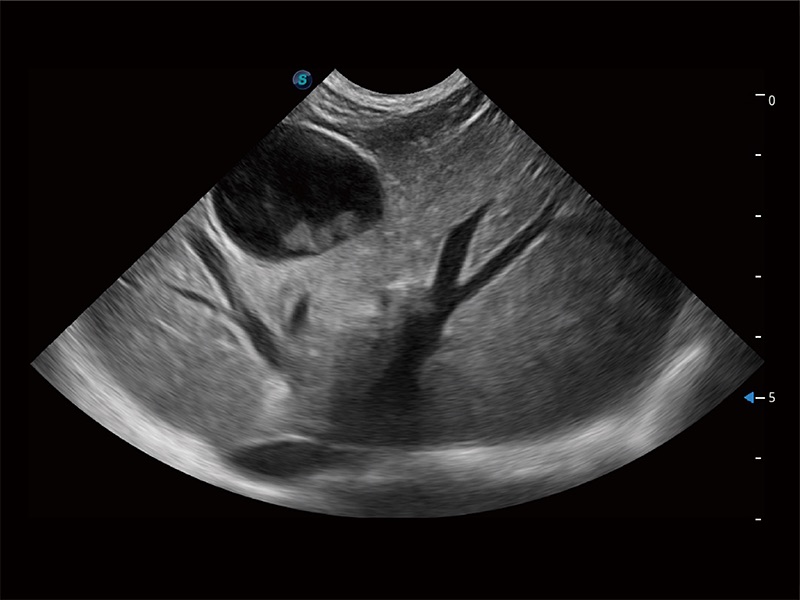

ProPet 80 配備了豐富的心臟探頭群、先進(jìn)的成像技術(shù)和專(zhuān)業(yè)的心臟測(cè)量工具,可幫助動(dòng)物醫(yī)生為不同體型和生理結(jié)構(gòu)的動(dòng)物提供心臟和心肌功能的全面評(píng)估。

ProPet 80 全新的動(dòng)物超聲智能軟件和豐富的探頭群,為動(dòng)物醫(yī)生提供了高清晰度和精細(xì)分辨率的圖像,無(wú)論在寵物、馬科、畜牧還是實(shí)驗(yàn)室動(dòng)物等應(yīng)用中都可以輕松應(yīng)對(duì),為您的日常工作帶來(lái)滿意的體驗(yàn)。